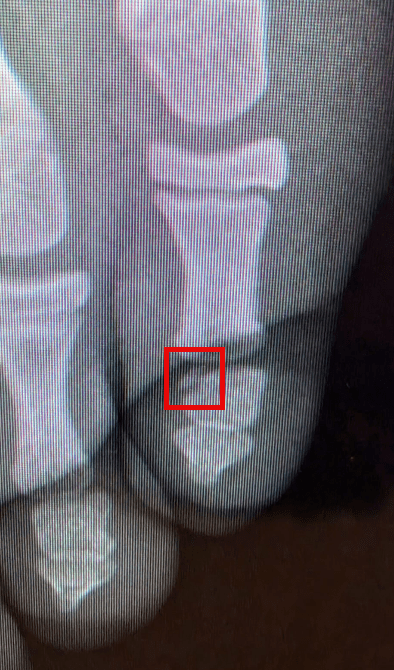

Our daughter Romy (she’s 11) broke her little toe from jumping on a trampoline.